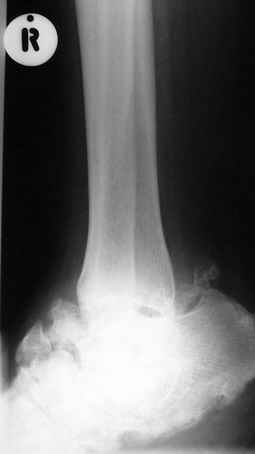

Кто шустрый - при какой патологии встречается так называемые "суставы Шарко"?Второе приобретение доктора Эмануэла мне понравилось своим романтическим названием: Candle bone - <кость-в-виде-оплывающей-свечи> : Просто редкая патология:

VR>Второе приобретение доктора Эмануэла мне понравилось своим романтическим названием: Candle bone - <кость-в-виде-оплывающей-свечи> : Просто редкая патология:

Мелореостоз

Под названием "мелореостоз" описано около 50 случаев врожденного заболевания скелета, выражающегося в совершенно

своеобразном одностороннем остеосклерозе костей одной только конечности. Можно не сомневаться в том, что

мелореостоз встречается далеко не редко; мы наблюдали свыше 20 случаев. Вполне естественно, что отдельные новые

казуистические наблюдения, не вносящие в науку никаких новых фактов и не возбуждающие новых мыслей и обобщений,

остаются неопубликованными.

Остеосклероз при этом заболевании захватывает не всю кость по окружности, а простирается слегка волнистой

полосой вдоль длинной оси конечности (рис. 223, К), переходя через линию суставов на другие кости. Таким образом,

может оказаться пораженной целая верхняя или нижняя конечность или больший или меньший ее периферический участок,

например, часть лопатки, полуцилиндр плечевой кости, часть цилиндра лучевой кости и скелет II пальца вместе с

лежащими по этой оси участками запястных костей или же часть - медиальная или латеральная - бедренной,

болынеберцовой кости с продолжением и расширением процесса на предплюсневые и плюсневые кости и соответствующие

по длиннику фаланги одного или нескольких, но никогда не всех пальцев. Описавшие эту болезнь в 1922 г. Жоани

(Joanny) и Лери (Leri) сравнивают остеосклеротические полосы с картиной, напоминающей стекающий со свечи и

застывающий стеарин или воск, отсюда и название "мелореостоз" - "стекающая вдоль конечности кость".